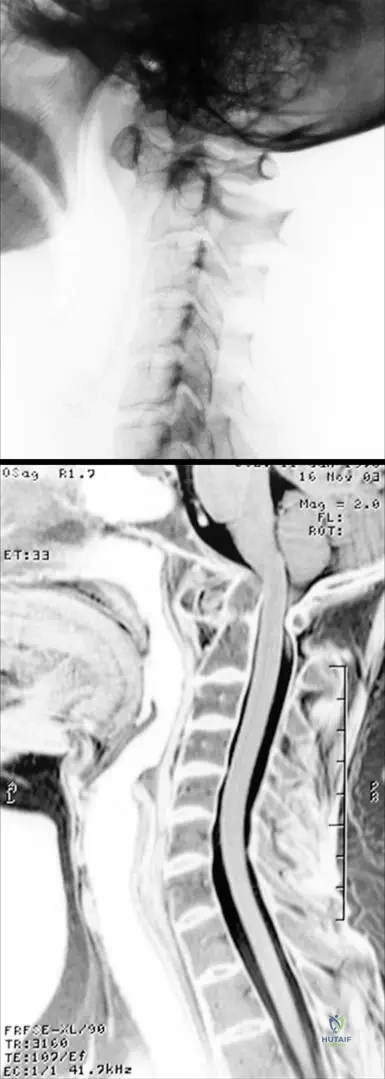

A 48-year-old female with early-stage rheumatoid arthritis reports mild neck stiffness. An X-ray and MRI of the cervical spine are performed. The images show incipient atlanto-axial synovitis with moderate subluxation, but the MRI confirms a normal liquor space around the spinal cord without cord involvement.

View Answer & Explanation

Correct Answer: D

Rationale: Even in early RA, atlanto-axial synovitis and moderate subluxation can occur. Given that the liquor space is normal and there is no cord involvement, immediate surgery is not indicated. However, the potential for progression to severe subluxation and cord compression necessitates close monitoring. The main distractor, A, is incorrect because surgical indication is typically based on severe subluxation (e.g., posterior atlantodental interval <14mm) or neurological signs, neither of which are present here.

Question 79

A 72-year-old male with severe, late-stage rheumatoid arthritis presents with progressive gait disturbance and upper extremity weakness. MRI of the cervical spine reveals severe atlanto-axial subluxation with dorsal and cranial displacement of the dens, resulting in spinal cord compression. The distance between the posterior wall of the dens and the anterior wall of the posterior arch of the atlas measures 12 mm.

Correct Answer: C

Rationale: In late-stage RA, severe atlanto-axial subluxation can lead to spinal cord compression, which is a life-threatening complication. The text explicitly states that when the distance between the posterior wall of the dens and the anterior wall of the posterior arch of the atlas is 14 mm or less, surgical indication is established regardless of neurological signs. This patient's measurement of 12 mm falls within this critical range. Neurological signs are generally not reversible. The main distractor, A, is incorrect as conservative management is insufficient for severe subluxation with cord compression and a critical measurement.